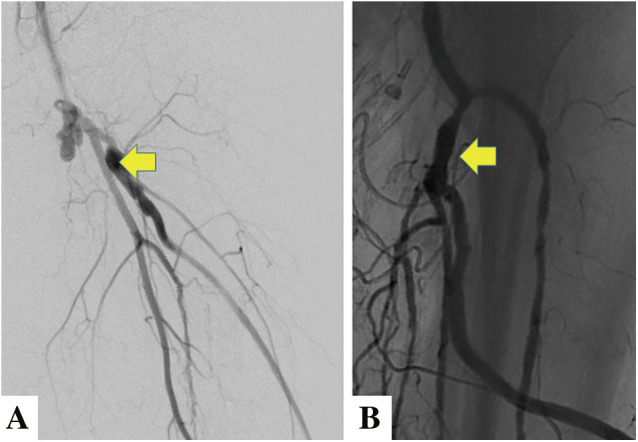

Infrapopliteal revascularization is generally performed for patients with chronic limb-threatening ischemia. As with revascularization in other fields, the indications for endovascular treatment (EVT) have expanded in recent years due to advances in endovascular devices and techniques. However, the optimal revascularization method must be selected based on (1) patient risk, (2) limb severity, and (3) anatomical pattern of disease. Therefore, vascular surgeons need to understand the characteristics of EVT and surgical treatment and improve their technical skills in both procedures. Here is an overview of the current methods of revascularization. (This is a translation of Jpn J Vasc Surg 2024; 33: 61-65).